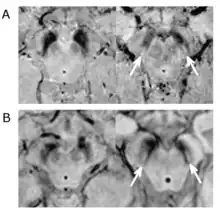

Le diagnostic de maladie de Parkinson est habituellement clinique. En théorie, la certitude du diagnostic n'est obtenue que par l'étude histologique du cerveau mais les critères diagnostiques actuellement définis permettent de faire le diagnostic sans trop de difficultés. Le scanner cérébral par tomodensitométrie des personnes atteintes de la maladie de Parkinson est habituellement normal[121]. L'imagerie par résonance magnétique sensible au fer (IRM T2*) peut être utilisée dans un cadre diagnostique. En effet, le fer peut être témoin de la mort cellulaire et le signal T2* diminue en présence de fer tandis que son inverse (R2*) augmente[122]. Dans la maladie de Parkinson, il existe une concentration en fer trop importante par rapport à la moyenne pour le même groupe d'âge au sein de la substance noire du fait de la perte de neurones dopaminergiques[123]. De plus, l'imagerie pondérée en fonction de la susceptibilité est elle aussi un marqueur fiable de la présence de fer intracérébral en étant à la fois sensible et spécifique à la maladie[124]. L'IRM T2* et l'imagerie pondérée en fonction de la susceptibilité sont toutes deux capables d'afficher le signe d'effacement de la queue d'hirondelle (swallow tail) dans la substance noire dorsolatérale. La tomodensitométrie et l'IRM sont également utilisées, en pratique clinique, pour écarter d'autres maladies pouvant engendrer un syndrome parkinsonien telles que l'encéphalite, les AVC chroniques, les tumeurs des ganglions de la base et l'hydrocéphalie[121].